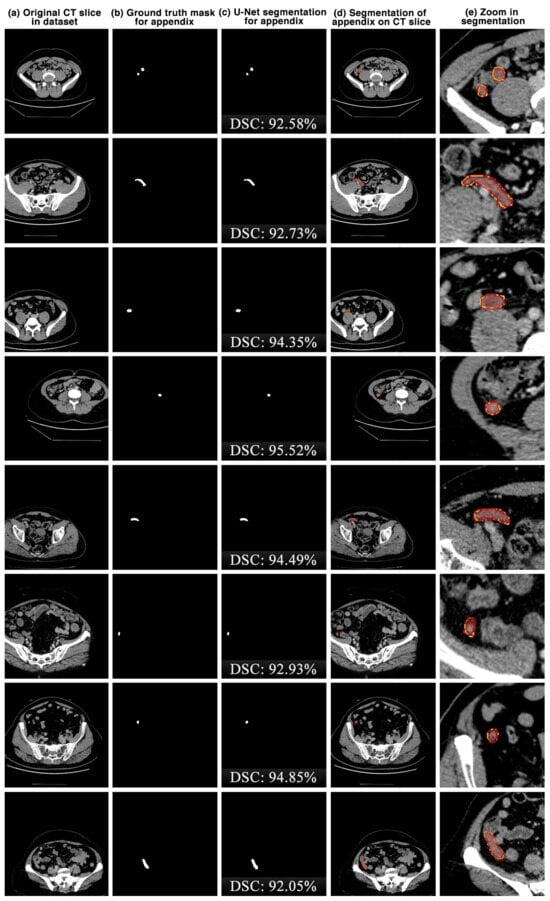

The appendix regions successfully detected and segmented on CT slices using the proposed U-Net deep learning architecture during the experimental studies are shown in Figure 6. While the mask of an original CT slice in Figure 6a containing the appendix region delineated by the expert is shown in Figure 6b, the segmentation of the appendix by the proposed U-Net deep learning architecture is shown in Figure 6c along with the DSC score. On the other hand, the overlap of the expert mask and the U-Net segmentation on the CT slice is also shown in Figure 6d and its zoomed version is shown in Figure 6e. As can be seen, the proposed U-Net-based deep learning architecture is very successful in segmenting the appendix CT scans and is very close to the expert GTs. Some examples of the segments that the proposed model has difficulty in detecting are shown in Figure 7. When analysing Figure 7, it is clear that the model cannot successfully detect some slices. The lack of success in these slices can be attributed to the fact that the appendix region is close to or adjacent to other areas, or the boundaries of the region are similar to those of the neighbouring areas. Such cases stood out as instances where the boundaries of the appendix were blurred and the model was unstable.

Figure 6.

The appendix regions successfully detected and segmented on CT slices using the proposed U-Net deep learning architecture during the experimental studies. Red: ground truth mask for appendix, yellow: U-Net segmentation for appendix.